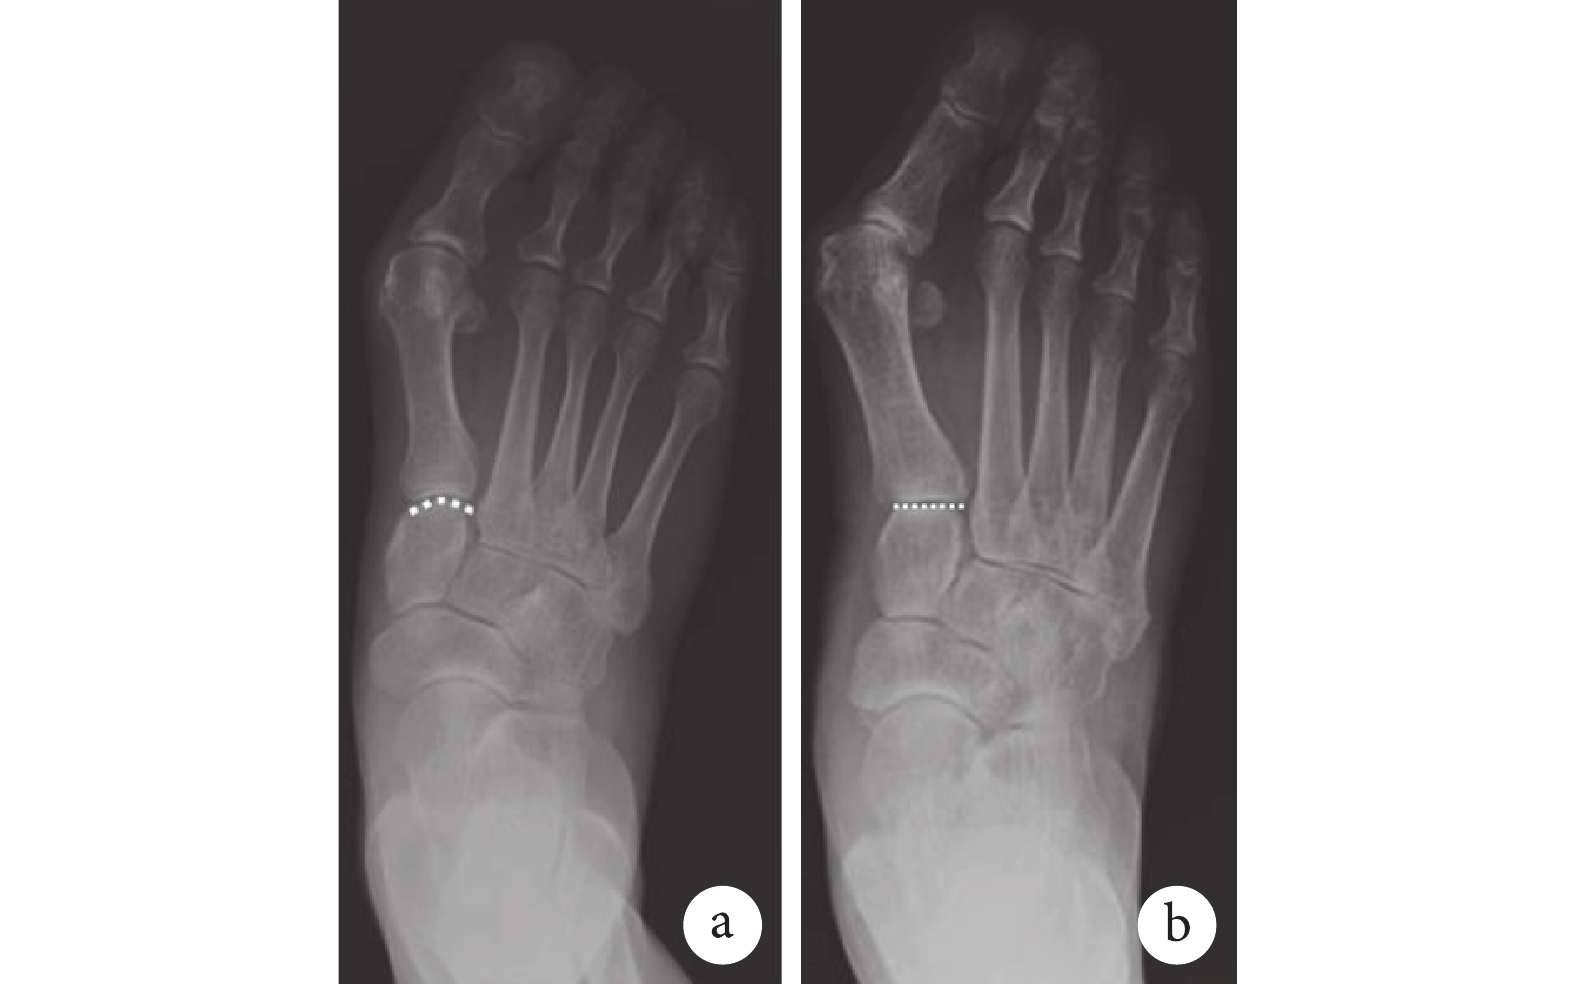

利用病案查詢系統和影像科計算機存檔與傳輸系統,收集我院2018年1月—2021年2月拍攝的足負重正位X線片。標準足部負重正位片投射時患者站立于接收板上,球管中心線與地面垂線間夾角為15°[12],基本與足背垂直(圖1)。由2名骨科高年資主治醫師分別閱片,剔除不符合標準的X線片,意見不同時討論決定,如還有異議則由1名副高職稱醫師決定。